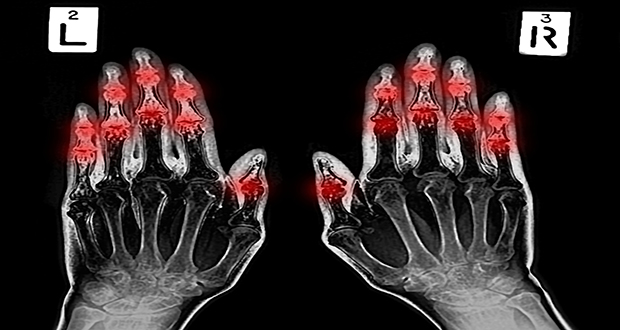

Arthritis is the inflammation of a joint, with osteoarthritis and rheumatoid arthritis the most common types. In the UK, 10m people are estimated to have arthritis. Osteoarthritis is caused by the breakdown of joint cartilage and underlying bone, whereas rheumatoid arthritis is a long-lasting autoimmune disorder that affects joints.